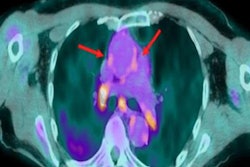

All patients showed metabolically active lesions in both lungs with FDG standard uptake values (SUV) between 2.0 and 12.7 (mean SUVmax of 4.2) and metabolically active mediastinal lymph nodes (mean SUVmax of 3.5, range 2.4-5.1) were noted in 13 (52%) patients, as well as significant CT lung findings.

A 71-year-old male diagnosed with COVID-19 in October 2020. After treatment, he was discharged from the hospital. He was readmitted to the hospital for respiratory failure in January 2021 and underwent F-18 FDG PET/CT. (A) Maximum intensity projection whole-body image and axial fused PET/CT show FDG-avid (SUVmax, 12.7) consolidation in the right lung (red arrow). Non-tracer-avid changes are noted in both lungs on CT. FDG-avid mediastinal lymph nodes (SUVmax, 4.4) (yellow arrow) were also noted. The patient was given steroids and pirfenidone for two months. He showed significant improvement in symptoms with no oxygen requirement. (B) Follow-up PET/CT reveals complete resolution of the lung lesion and non-avid residual fibrotic changes in both lungs (red arrow). Mediastinal lymph nodes also show a decrease in avidity (SUVmax, 2.5). Image courtesy of Yogita Khandelwal.Patients received methylprednisolone (a steroid) and pirfenidone (an antifibrotic drug), then underwent a follow-up scan between six and 12 weeks later to evaluate their response to treatment and assess residual lung damage.

Specifically, seven (32%) of these 22 patients were found to have active metabolic lesions in the lung parenchyma, with mean SUVmax dropping from 4.2 to 2.7. Also, five (23%) patients showed a mean SUVmax in metabolically active mediastinal lymph nodes dropping from 3.5 to 3.2.